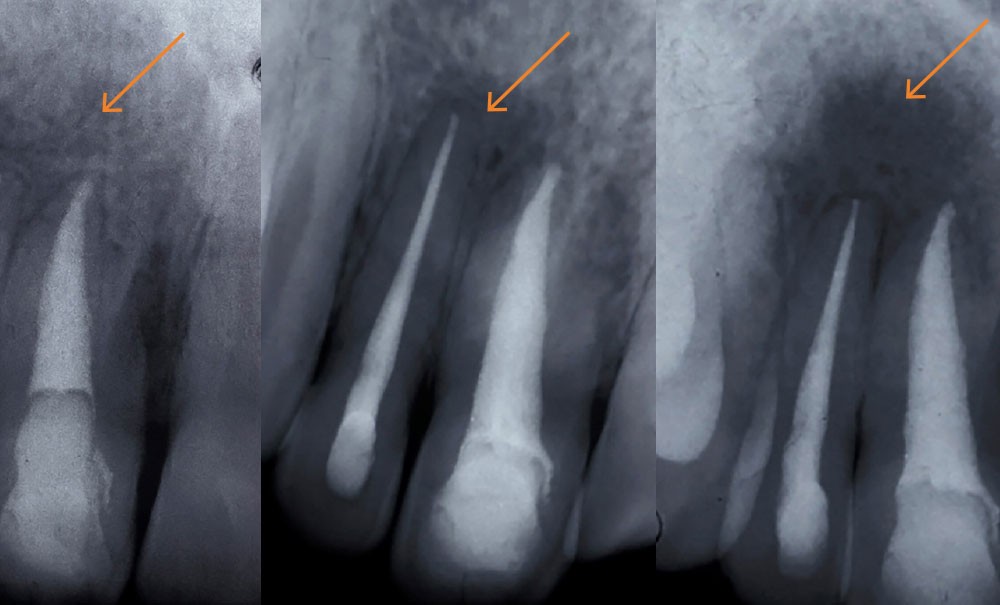

À l’âge de 7 ans, Anna fait une chute dans la cour de récréation et tombe de sa hauteur face contre terre. L’incisive centrale supérieure droite (la 11) est subluxée. Les parents de l’enfant consultent en urgence leur chirurgien-dentiste, le Dr A. Un certificat médical initial (CMI) est rédigé en respectant le formalisme.

Examen clinique

« J’ai constaté ce jour :

- à l’examen exo-buccal : une plaie de la lèvre supérieure…